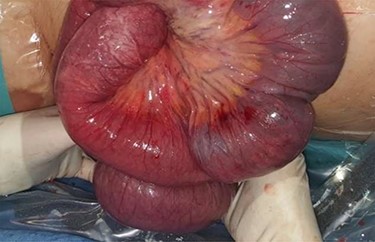

Physical examination presented normal vital signs. The abdomen was tender but lacked signs of peritonitis. Blood analysis revealed leukocytosis, neutrophilia and elevated lactate dehydrogenase. Obstetric ultrasonography (US) showed: fetus at cephalic presentation with good vitality, regular amniotic fluid volume, placenta without detachment. An abdominal computed tomography (CT) scan revealed proximal jejunal dilation caused by an ileoileal invagination and collapsed distal ileum (Figs 1 and 2). Betamethasone and atosiban were administered, and a supraumbilical laparotomy was performed. The intussusception in the common limb (80 cm distal to jejunojejunostomy) (Fig. 3) was reduced (Figs 4 and 5) with progressive and complete intestinal vascular perfusion (Fig. 6). The postoperative period was uneventful, and a caesarian was performed 4 weeks later. At the 45-month follow-up, there was no recurrence.

Retrograde intussusception of the common limb into the jejunojejunostomy.